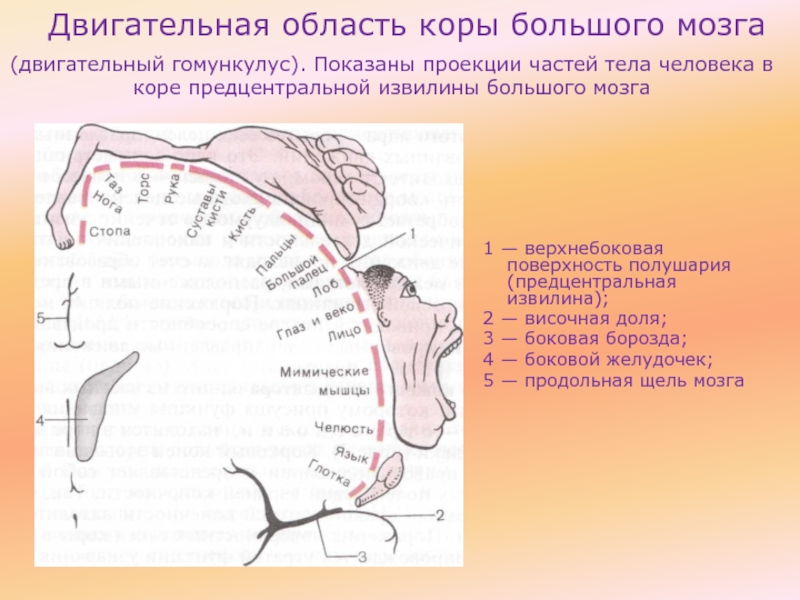

Схема чувствительных зон новой коры мозга